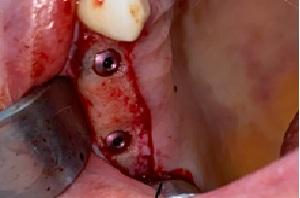

Before / After Results

Discover our patients transformations